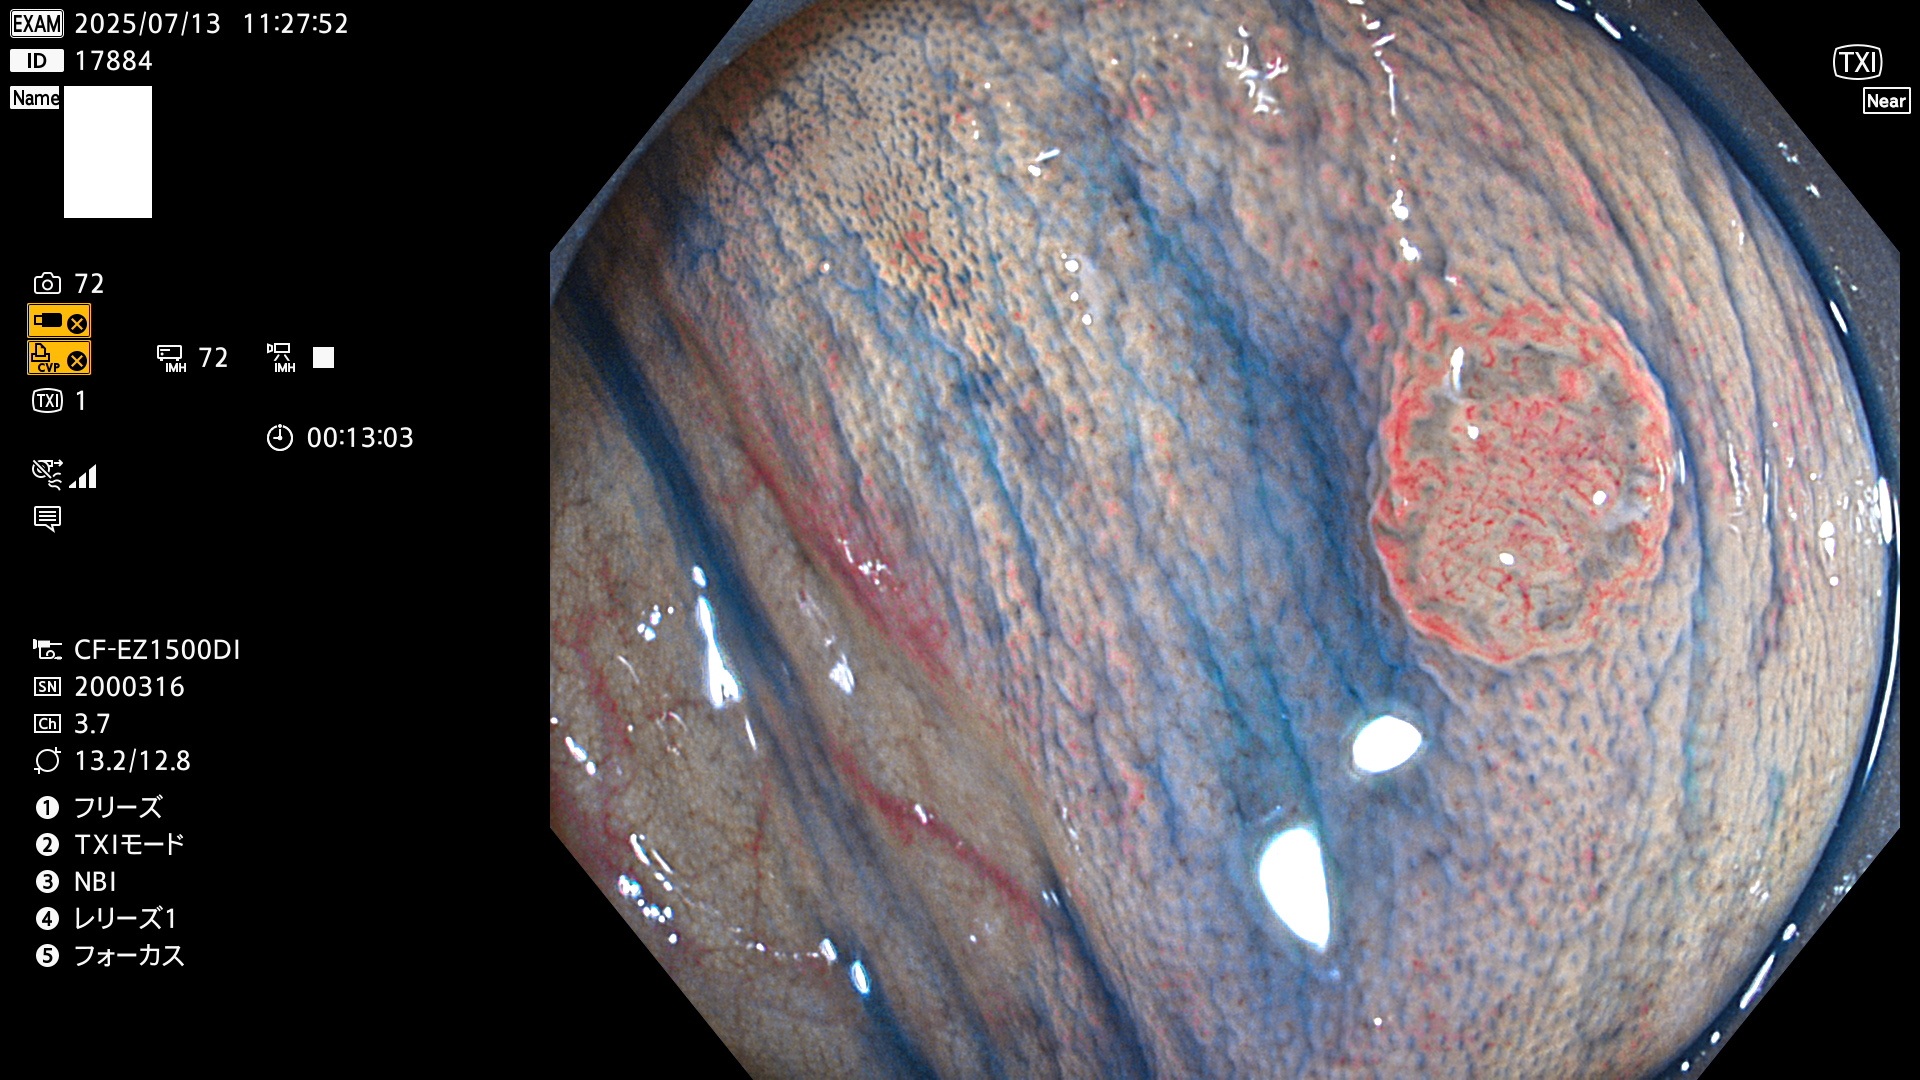

2025年7月10日〜7月13日の4日間(40件)15個 (Uc_ADR=15/40=38%)